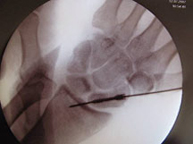

The scaphoid bone is the most common fracture of the carpal bones after falls with an outstretched hand. This is a characteristic injury in sports such as motorcycling, cycling and skateboarding where they can suffer high speed injuries. The pain is located along the axis of the thumb and the tenderness in the wrist area (snuffbox) is extreme. Displaced fractures usually required surgically stabilization through the introduction of percutaneous intraosseous screws.